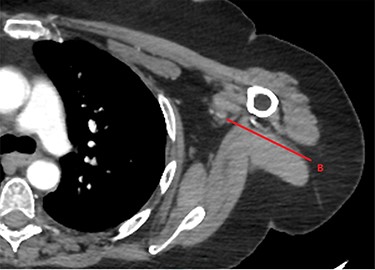

CTA of left upper limb in the transverse plane. B—axillary artery without contrast showing occlusion due to embolism as evident in transverse imaging at B-line (see Fig. 2).